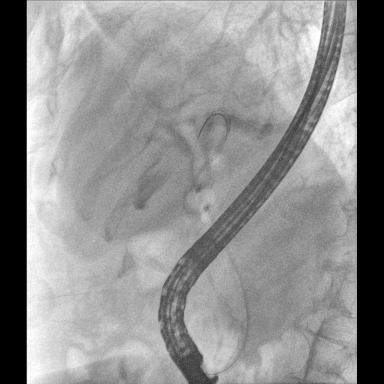

具備血管造影及數(shù)字減影(DSA)、路徑圖(Road-map)、透視、攝影等功能。 廣泛適用于介入科、血管外科、腫瘤科、消化內(nèi)科及骨科等多個臨床科室,典型應(yīng)用包括:TACE(肝腫瘤栓塞與化療灌注術(shù))、心臟起搏器置入術(shù)、四肢動脈造影術(shù)、下肢靜脈濾器置入術(shù)、ERCP(經(jīng)內(nèi)鏡逆行胰膽管造影術(shù))等。

核心DSA軟件可實時生成高清血管影像,結(jié)合路徑圖功能,在手術(shù)中為醫(yī)生提供血管導(dǎo)航。

預(yù)留高壓注射器聯(lián)動接口,C形臂開始透視時,高壓注射器自動注入造影劑,提高術(shù)中造影減影效率,減少醫(yī)師手推造影劑所受到的輻射暴露劑量。